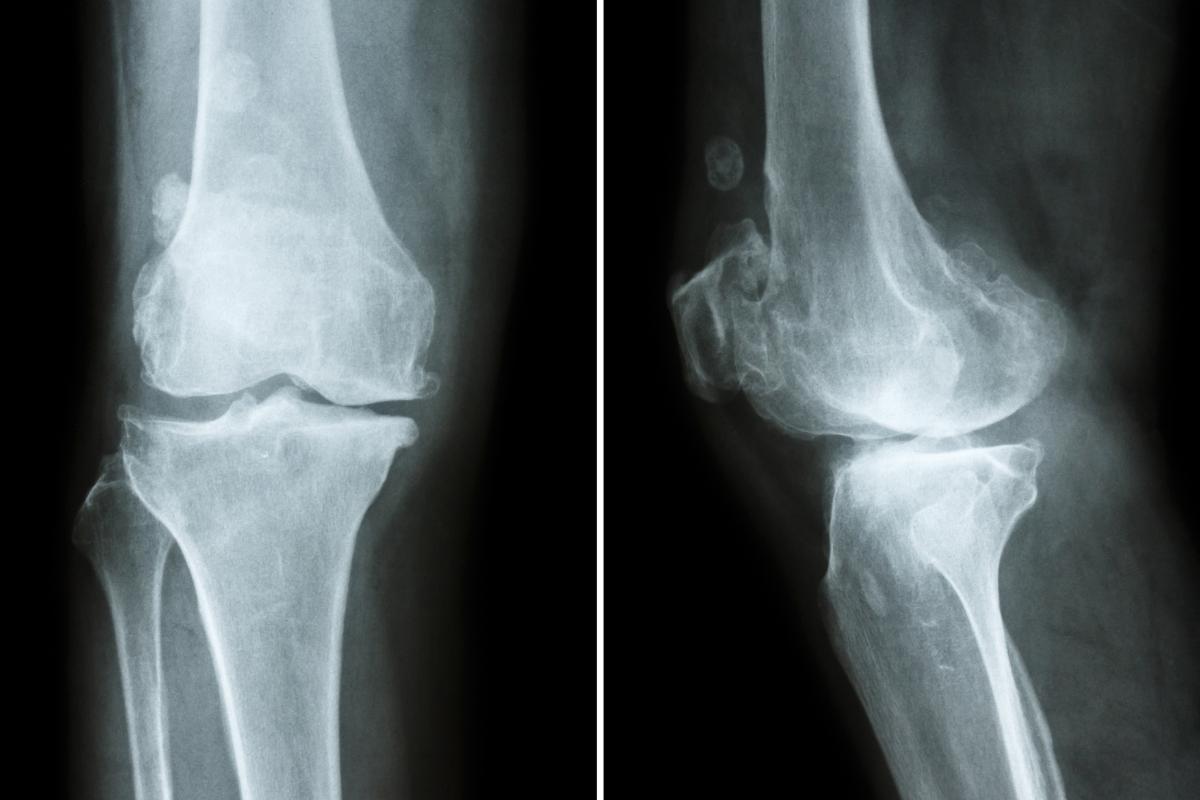

Rotura del ligamento cruzado

Es una de las causas más frecuentes de cojeras en perros pequeños viejos. Es la rotura total o parcial de uno de los ligamentos de la rodilla y afecta a una de las principales estructuras estabilizadoras de esta. El ligamento cruzado anterior une el fémur con la tibia; es por ello que, cuando se ve afectado, se puede apreciar que a tu perro le falla una de las patas traseras, ya que es crucial para mantener la estabilidad de la articulación.

Tratamiento

Existen varios tipos de tratamientos dependiendo, principalmente, de la edad del perro afectado. La solución definitiva es quirúrgica, pero en caso de no ser posible la cirugía existe un tratamiento de soporte. Los antiinflamatorios y el fortalecimiento de los músculos pueden reducir el dolor y la cojera.

Será el veterinario quien nos aconseje la mejor la opción para nuestro perro. En este post compartimos todos los detalles: "Rotura del ligamento cruzado en perros - Cirugía, tratamiento y recuperación".